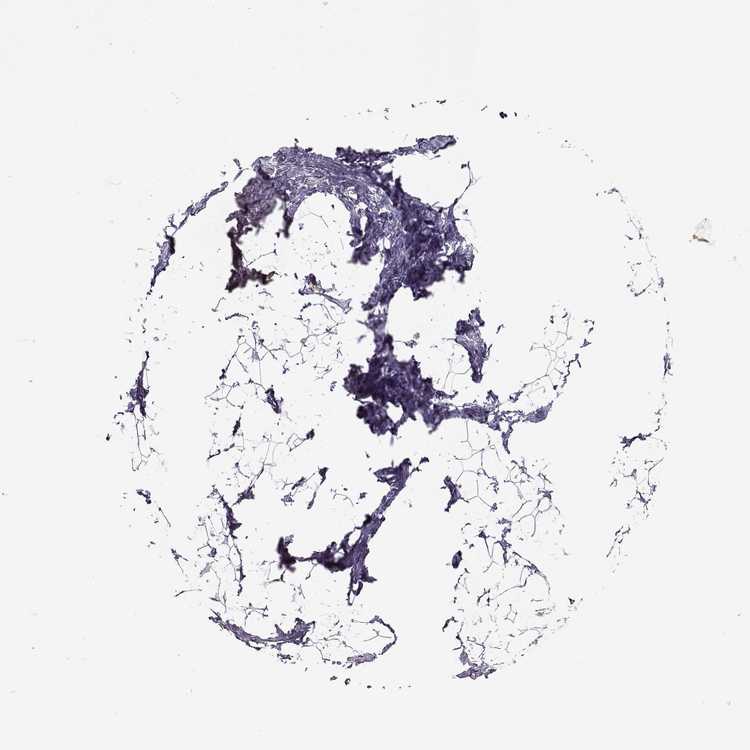

BREAST - Antibody stainingi

Antibody staining in the annotated cell types in the current human tissue is reported as not detected, low, medium, or high, based on conventional immunohistochemistry profiling in selected tissues. This score is based on the combination of the staining intensity and fraction of stained cells.

Each image is clickable and will lead to virtual microscopy that enables deeper exploration of all samples and also displays staining intensity scores, fraction scores and subcellular localization as well as patient and tissue information for each sample.

Antibody HPA014314Antibody HPA056908Antibody CAB037336

Glandular cells LowLowNot detected